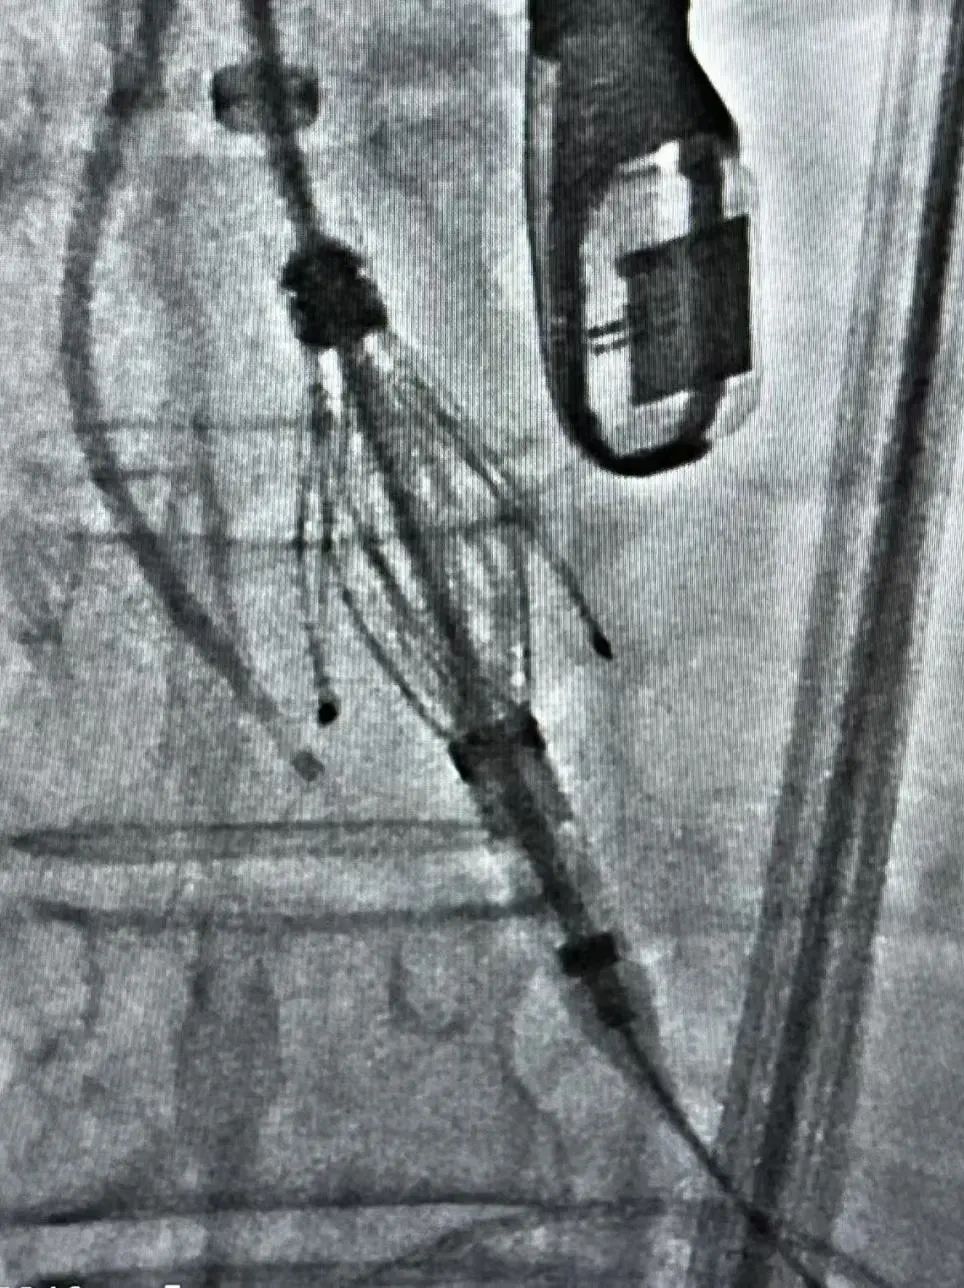

患者全麻后植入Safari预塑弯导丝,猪尾根部造影后,置换MP导管,使用TaurusTrio THV27进行植入,首先将TaurusTrio 导引鞘推进到STJ上方。输送系统装载27规格瓣膜,到达STJ上初始释放位,回撤长鞘到降主动脉位置。使用调弯功能调整轴向,推进1cm展开定位键后,调整DSA验证定位键位置,可进行整体旋转瓣膜进行瓣窦对齐,确保在coplanar View三个定位键与原生窦对齐,推进瓣膜使定位键进入窦底,逐一造影验证后,在起搏下释放。完成植入后造影结果显示重度主动脉反流消失,无瓣周漏,瓣膜释放形态较理想,且释放后无新发起搏器植入指征,顺利结束手术。

▲释放后造影